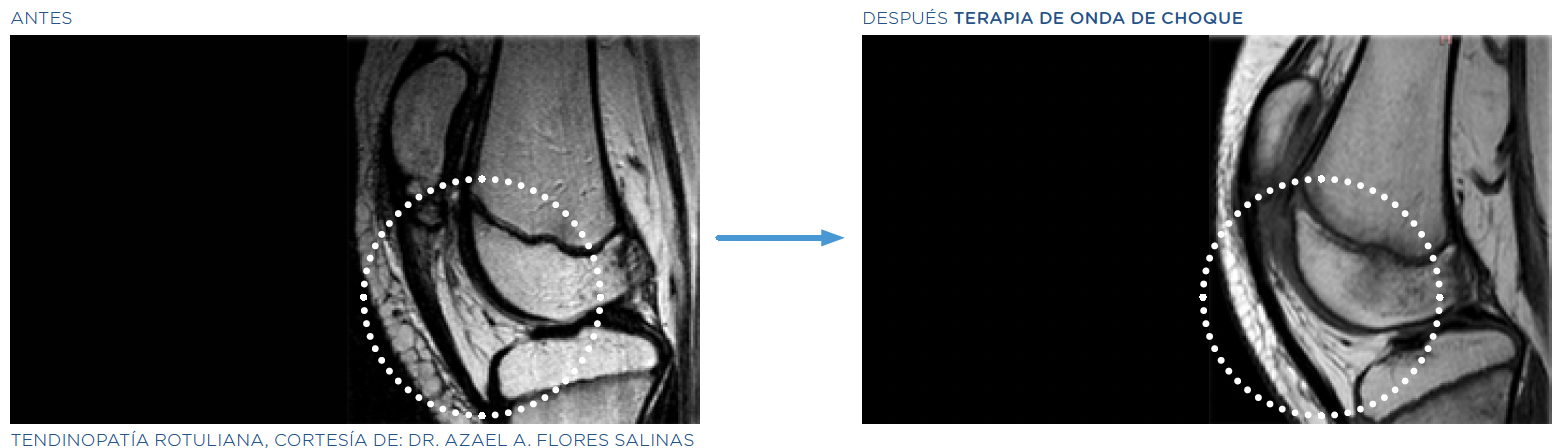

Nuestra nueva terapia de ondas de choque es la mejor alternativa para tratar condiciones crónicas que causan dolor, sin necesidad de cirugía o de tratamientos que generen la incapacidad temporal del paciente.

Esta terapia es la única en el mercado que actúa en el tejido afectado mediante estimulación celular profunda, favoreciendo la regeneración y alivio. Por ello, es ideal para darle tratamiento eficaz y definitivo a: